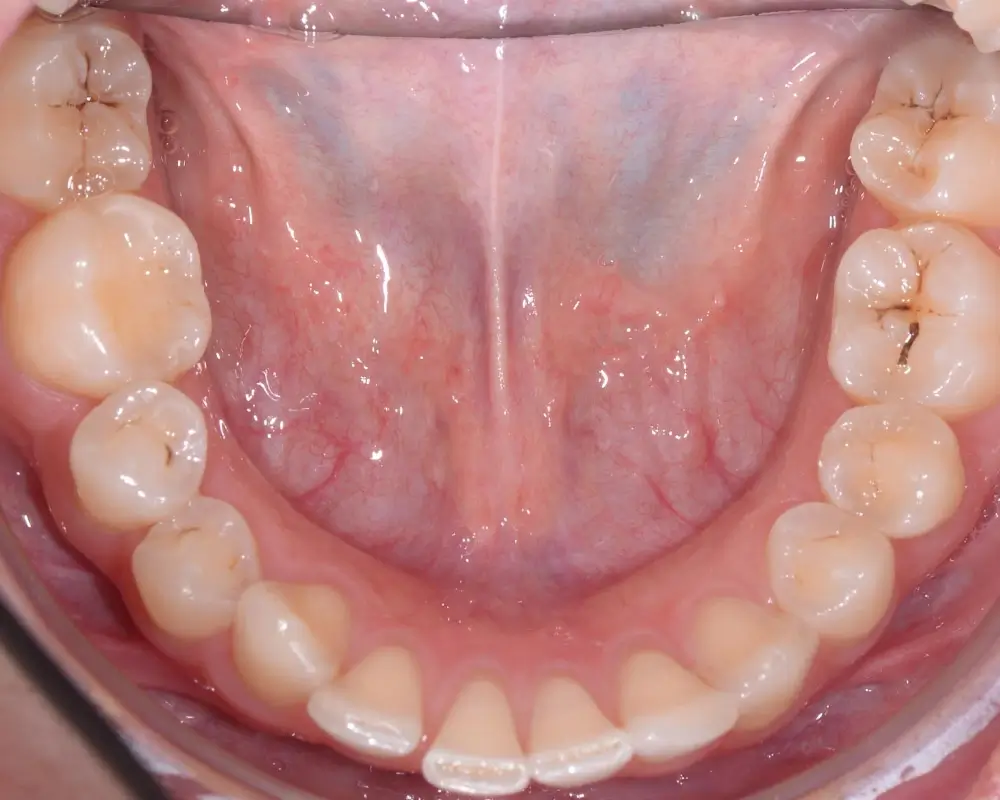

Дистальный прикус - Кейс 4

Эффективность устранения дефекта прикуса посредством элайнеров FlexiLigner.

26

Количество кап НЧ

18

Количество кап ВЧ

Результаты лечения